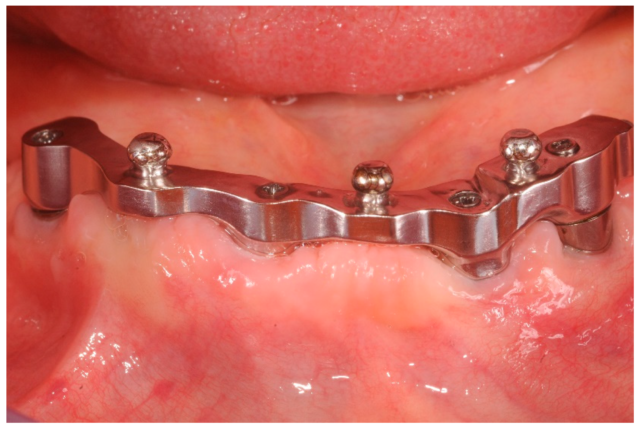

B. Implant-Supported Overdenture

✪Denture is fully supported by implants, not by gums.

Needs more implants (usually 4–6) and rigid bar structure.

Feels more like a fixed prosthesis but still removable for cleaning.

3. Bar and Clip